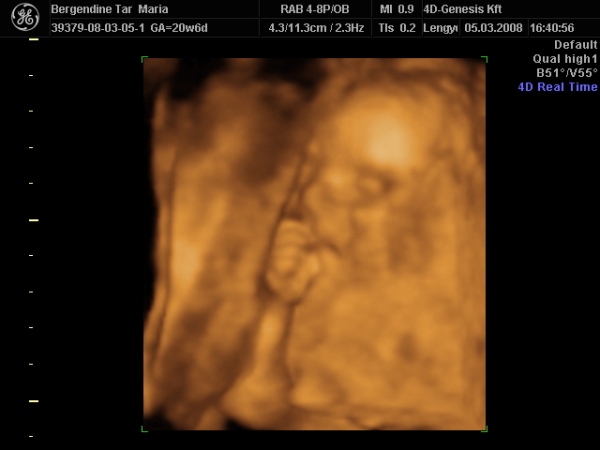

Hazaértem az ultrahangról, bemutatom nektek Zsófit:

Kép

édes a babád! Olyan mintha szopná az ujját, nem? :) A lányomnál már a 12 hetes ultrahangon úgy nézett ki, mintha szopná az ujját, aztán amikor megszületett, az első naptól kezdve szépen szabályosan szopta a hüvelykujját! Akkor lehet hogy mégis volt már gyakorlata benne???

Igen, a vizsgálat alatt csak néhány képen nem tömi az ujját a szájába. :lol:

végig ezzel volt elfoglalva. :lol: :lol: